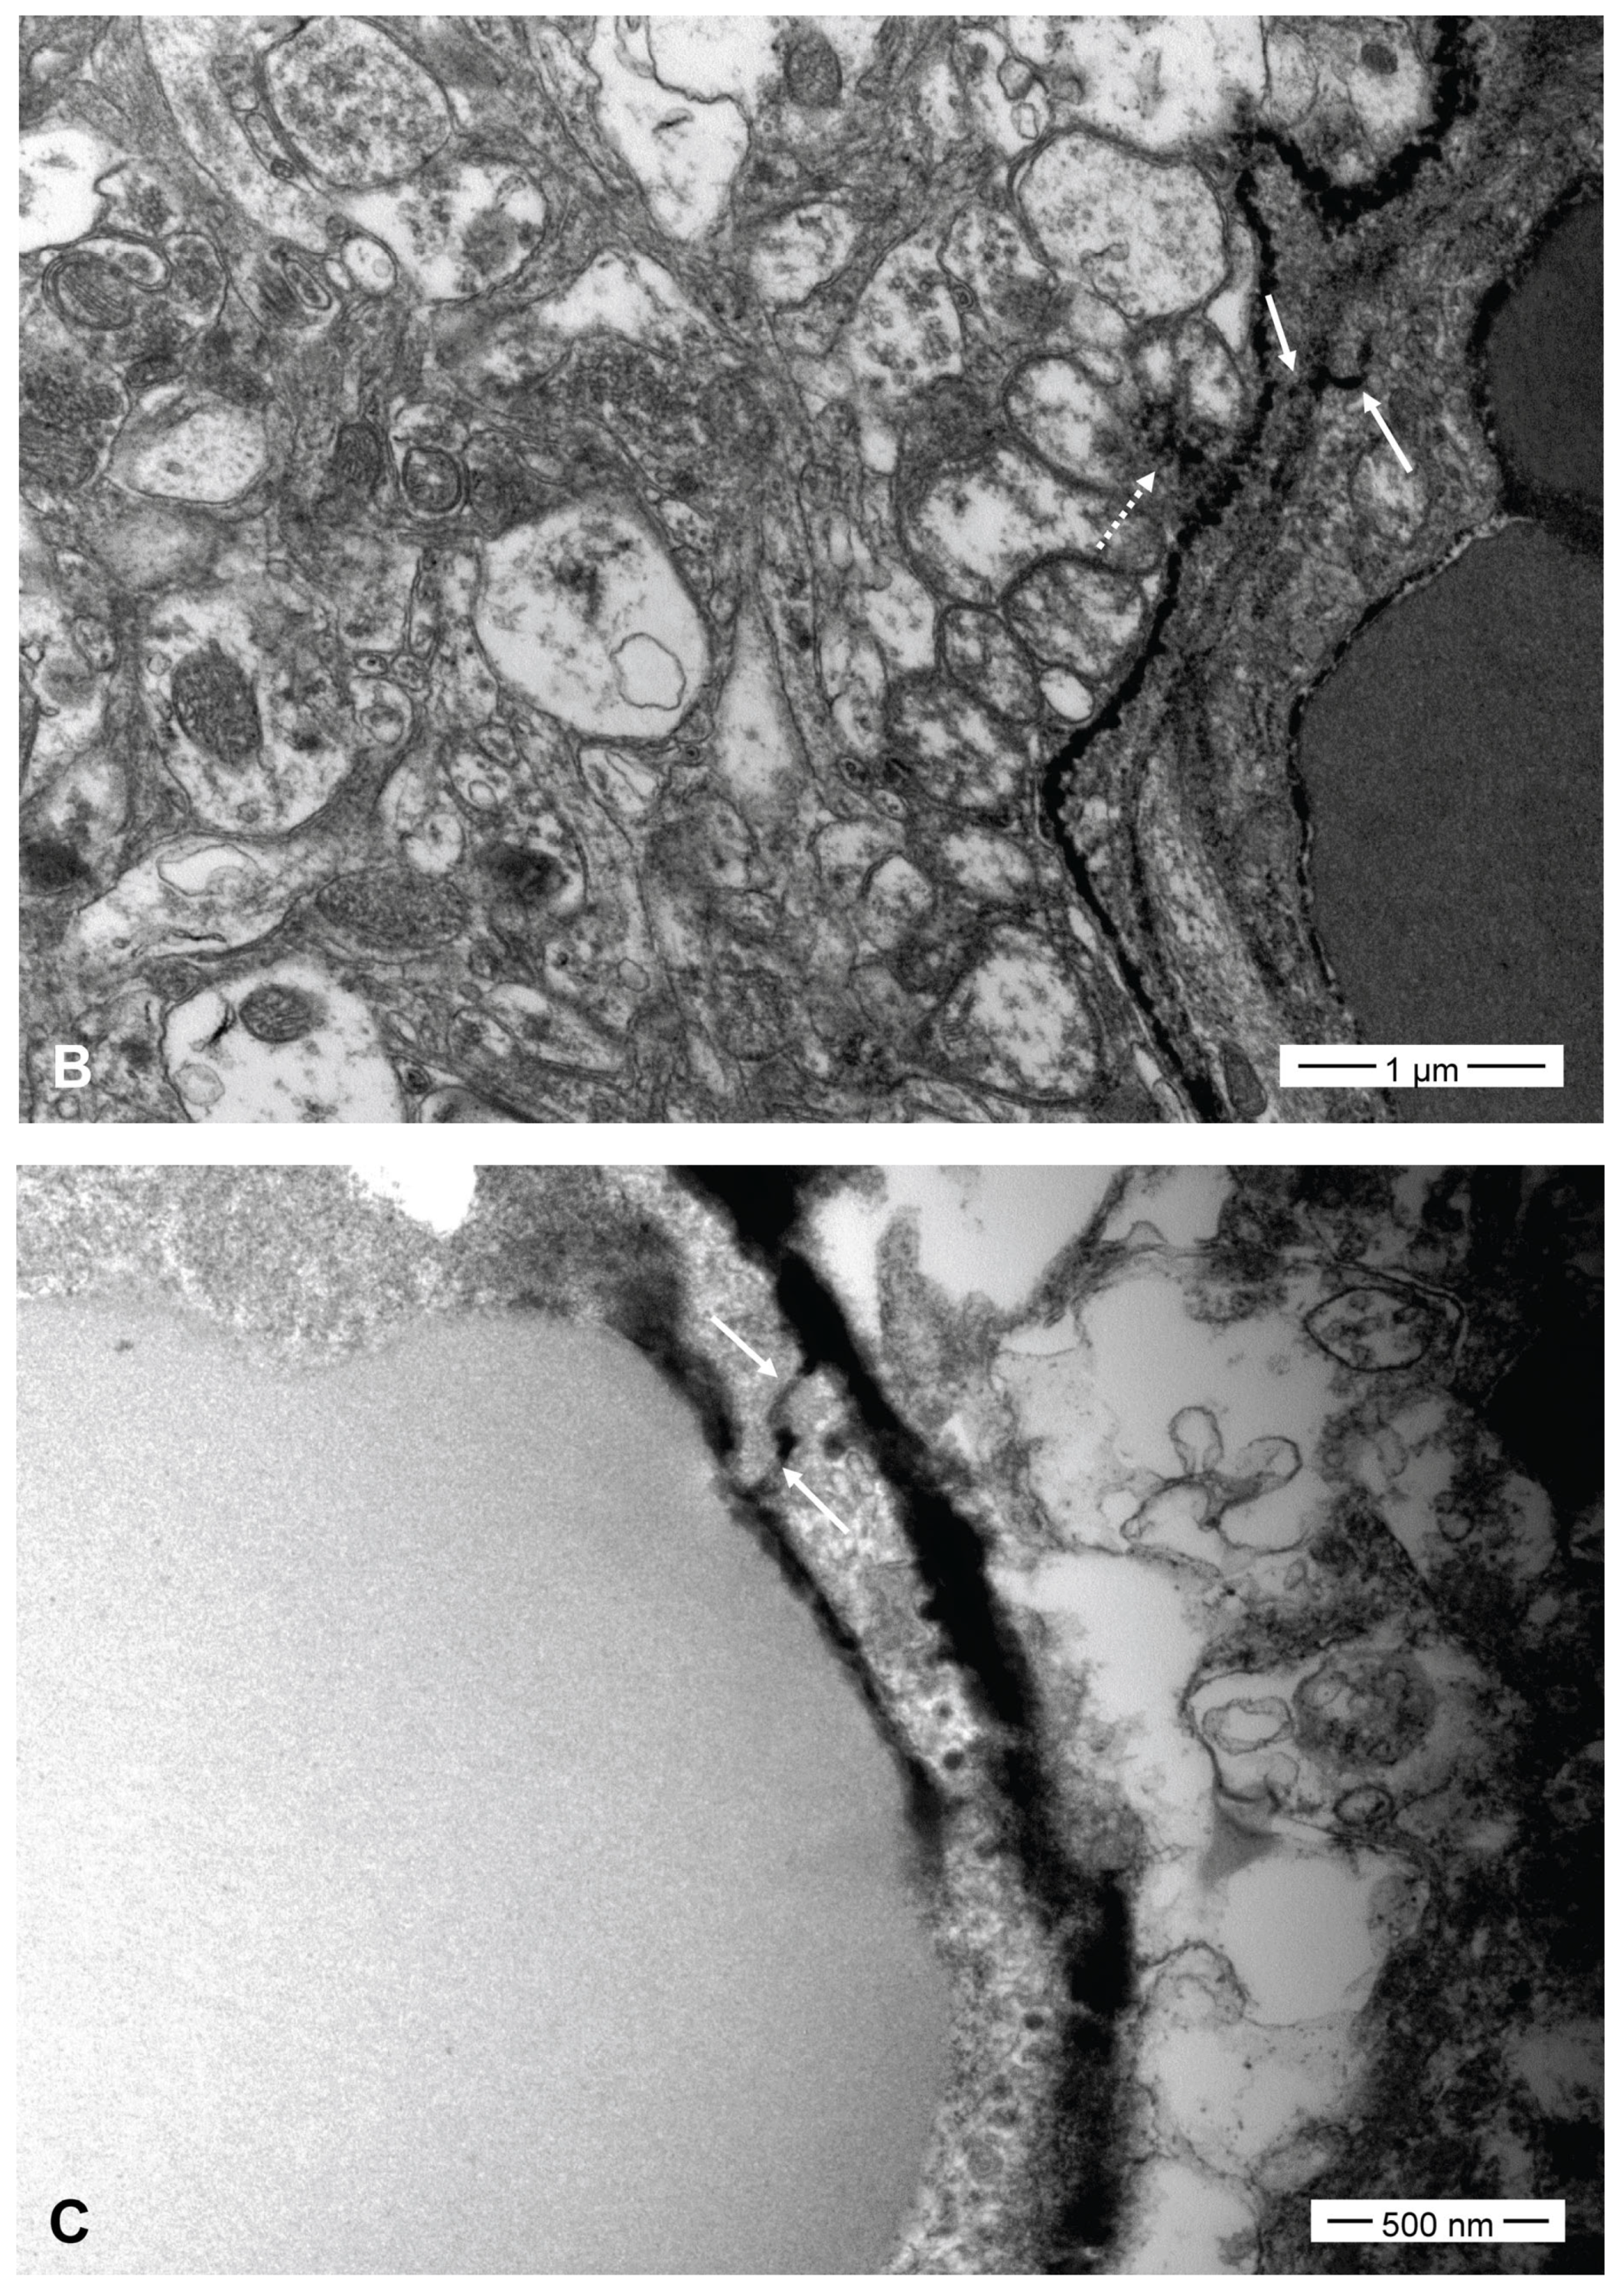

Tight junctions and the neural interstitium were filled with contrast medium (lanthanum) in all five SFA emulsion groups 1 h after each SFA emulsion infusion (Figure 6). The interstitial spillage of lanthanum occurred mainly around the capillaries. The widths of the tight junctions filled with lanthanum varied from 4 to 80 nm and were nonspecific in the five SFA emulsion groups. Transcytotic vesicles containing lanthanum were not evident.

BBB opening and enhanced drug delivery using intra-arterial infusion of fat emulsion produced consistent and reproducible results, although the degree differed according to the fat type. Both triolein and oleic acid were used to create fat embolism models. Non-esterified oleic acids bind to albumin and are nontoxic. However, free fatty acids are toxic to all tissues, especially capillaries [14]. However, the toxicity, intra-arterial, and intravenous effects of SFAs remain unclear. The pathogenesis of BBB opening due to fat is believed to involve a combination of mechanical and biochemical reactions [29]. The biochemical theory states that intravascular fat embolized in the lungs is converted into free fatty acids by pulmonary lipases. Free fatty acids disrupt capillary function, leading to edema, hemorrhage, and atelectasis, resulting in local inflammatory and toxic reactions. The mechanical theory states that fat occludes vessels and causes infarction. The large fat droplets mechanically disrupt the endothelium [30]. Clinical and experimental cerebral bolus fat embolisms revealed infarctions due to mechanical vascular occlusion [30]. However, the results of embolization with bolus fat or fat emulsion are quite different. In emulsions, fat particles are too small to occlude the vessel mechanically; hence, the biochemical theory is more likely to be the underlying mechanism for the results obtained. In a morphological study, a triolein emulsion opened the tight junctions of the brain endothelium, resulting in a paracellular drug delivery pathway [28]. In the present study, TEM revealed similar findings in all five SFA groups. The tight junction opens, as indicated by the filling of lanthanum contrast. Neural interstitial spillage of the contrast agent was a subsequent finding of tight junction opening due to the action of the SFA emulsion on the endothelium. Our TEM results for open tight junctions are also quite similar to those of previous studies on neutral fat emulsions on the endothelium and unsaturated fatty acid emulsions [27]. The diameter of the opened tight junction was 4–80 nm, was non-specific in the five SFA emulsion groups, and was similar in size to that of triolein (20–30 nm) [28]. However, in contrast to the triolein emulsions, transcellular vesicles were not evident in the present study. TEM results revealed a morphological mechanism by which fat emulsions open tight junctions. However, the exact molecular mechanisms underlying tight junction opening by fat emulsions remain unknown. We suspect that electric stimulation or charge change by fat electrophysiologically disrupts the tight junction bonding proteins.

Figure 6. Transmission electron microscopy (TEM) of the five SFA emulsion groups at 1 h after each emulsion infusion. The tight junction (arrows) was filled, and the neural interstitium (dot arrows) was spilled with the contrast media in the butyric ((A), ×12,000), valeric ((B), ×20,000), caproic ((C), ×40,000), enanthic ((D), ×50,000), and the caprylic acid ((E), ×25,000) groups.